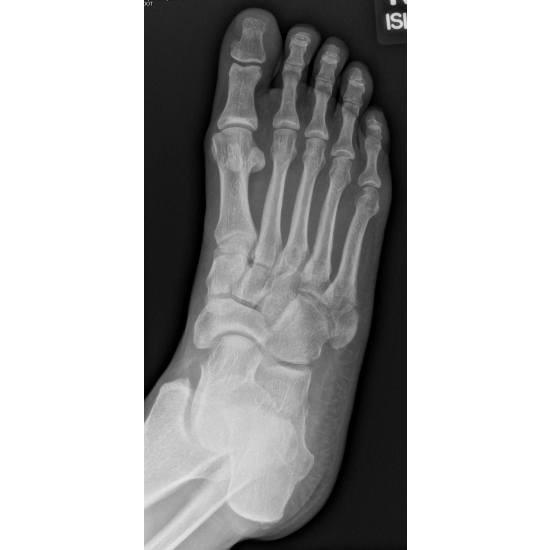

A 48-year-old-female runner complained of right lateral foot pain after running the bases at a softball game. She inverted her ankle on second base and felt a crack, but kept playing afterwards. She initially self-treated with a walking boot, but later went to the sports medicine clinic and was diagnosed with a right fifth metatarsal fracture. Case Photo #1 Case Photo #2